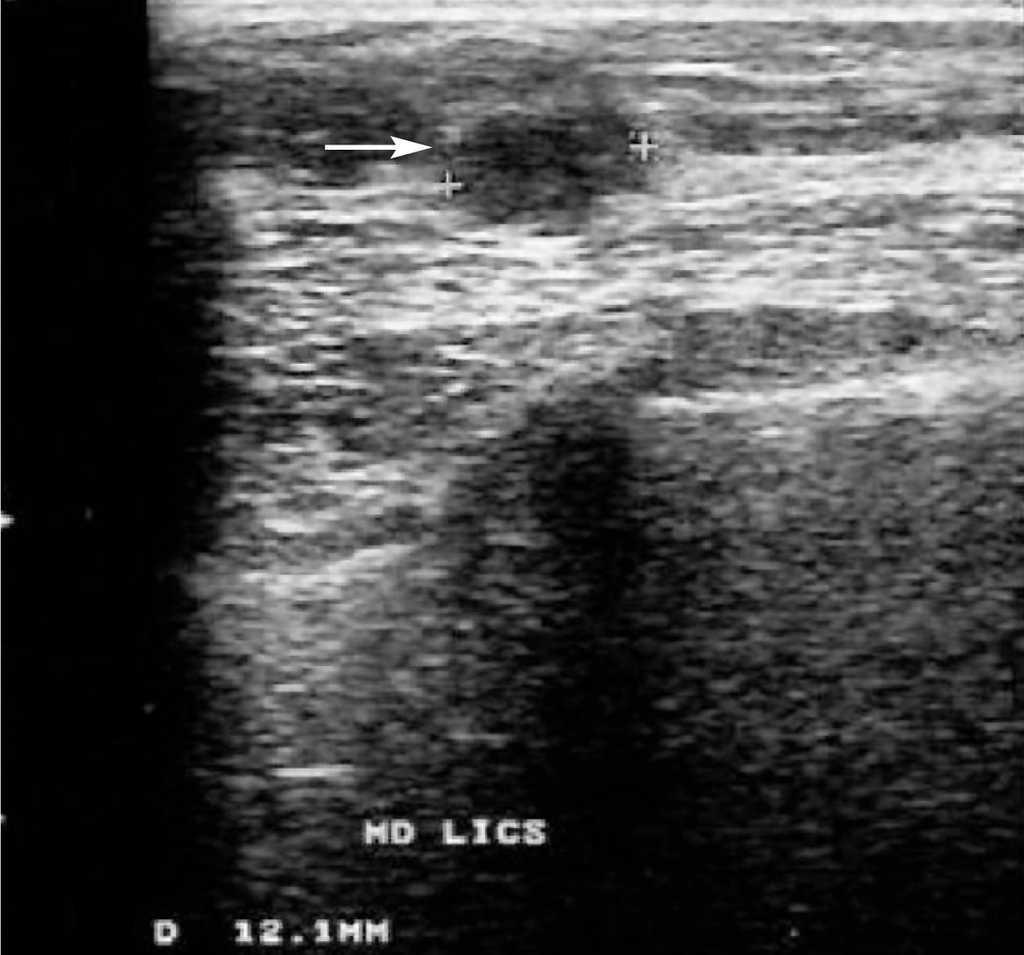

Ante la sospecha de neoplasia mamaria en MD se solicita la realización de una mamografía, ecografía y RM bilaterales. La mamografía muestra unas mamas con tejido fibroglandular de predominio denso con un nódulo espiculado de aproximadamente 1 cm en la LICS de MD. No se aprecian lesiones en MI (fig. 1). La ecografía bilateral confirma la presencia de un nódulo sólido de 1 cm con bordes irregulares, que coincide con la tumoración palpable en la LICS de MD. El estudio de MI no presenta hallazgos significativos (fig. 2). La RM bilateral informa de «... lesión nodular espiculada en LICS de MD con patrón de captación sugestivo de malignidad y que se extiende caudalmente a través de la línea intercuadrántica en presencia de pequeños nódulos satélites con patrones de captación similares que se aproximan hacia el pezón». La lesión nodular principal alcanza unos 14 mm de diámetro mayor, mientras que el conjunto de las lesiones satélites alcanzan unos 15 mm. En MI, «... captaciones significativas en fase arterial con presencia de un pequeño nódulo mal delimitado con un patrón de captación sugestivo de malignidad y con pequeñas lesiones satélite que se extienden caudalmente al igual que en la MD». Estas lesiones están en el cuadrante inferoexterno (CIE), en proximidad de la línea intercuadrántica inferior, a unos 2,5 cm del pezón (fig. 3). Ante el hallazgo de un área sospechosa en la RM de MI se decide solicitar una mamografía magnificada de cuadrantes inferiores de MI, que es informada como normal (fig. 4). Se decide biopsiar con aguja gruesa la masa de MD, y el resultado es de carcinoma ductal infiltrante (CDI) de grado 2.

Figura 2. Ecografía de la mama derecha. Se confirma la presencia de un nódulo sólido de 1 cm de tamaño con márgenes irregulares y cuya topografía coincide con la de la masa palpable (flecha).